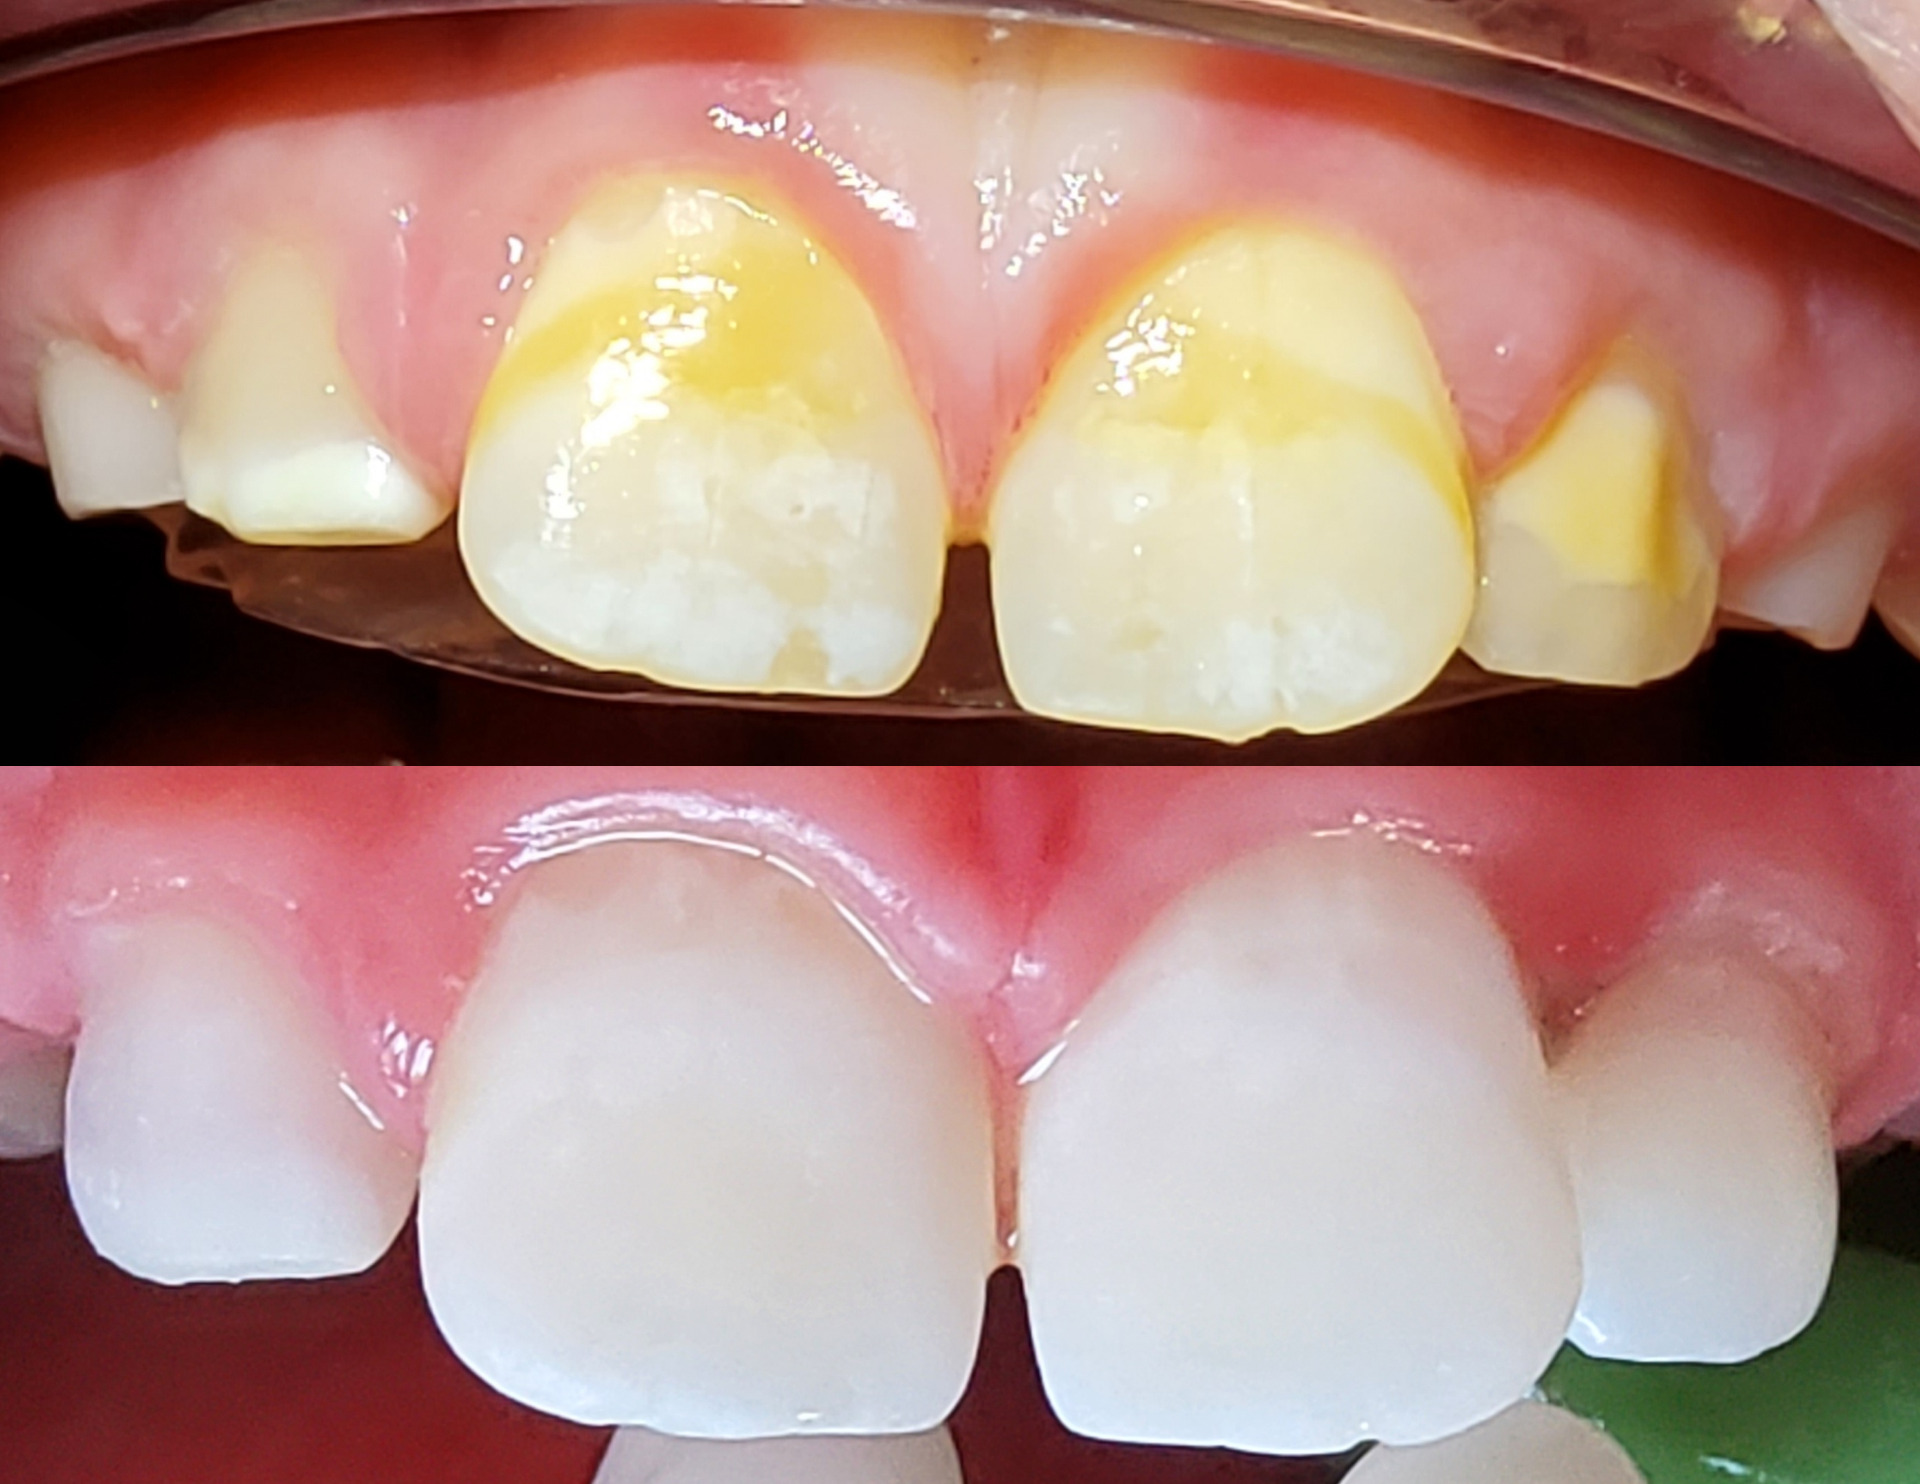

Apexification chez l’enfant

L’objectif de cette thérapeutique est de retirer le tissu pulpaire (« nerf ») nécrosé et d’induire au niveau apical, via un biomatériau …